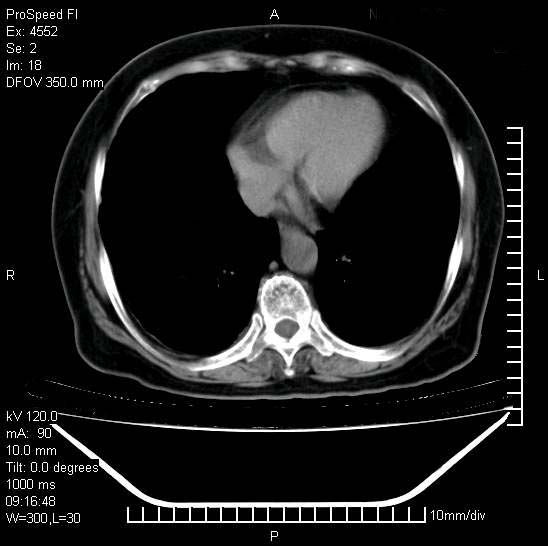

十几年前曾患肺结核,一周前突咳血约100ml,中性粒细胞稍高,诊断两上肺陈旧结核,下肺炎症,给予抗炎治疗,近几日晚上高热,39度,仍咳少量血,4天前ct及今天ct上传。

[face=黑体]8月30日[/face]